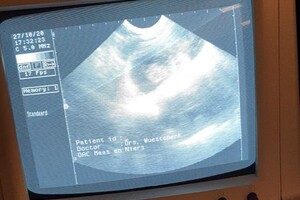

de dierenarts mocht Dakota eerst scheren, dit had ze nog niet eerder meegemaakt, maar ze vondt het niet zo erg, daarna heeft de dierenarts de scan gemaakt:

Ze is drachtig. het blijft moeilijk te zien hoeveel puppy's we kunnen verwachten, maar de dierenarts gaf aan dat we een mooi nest krijgen: niet te groot en niet te klein nest, ze ging uit van 4 a 5 puppy's. Dierenarts verwacht dan ook geen complicaties en een natuurlijke bevalling.